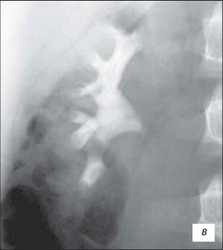

Висхідна цистографія

На даній рентгенограмі спостерігаємо активно-пасивний міхурово-сечовий рефлюкс зліва 4 ступені. Виражена дилатація чашечко-мисочкової системи, деформація чашок.

а – у фазі максимального наповнення сечового міхура, пасивний рефлекс; б – у фазі сечовипускання, активний рефлекс.